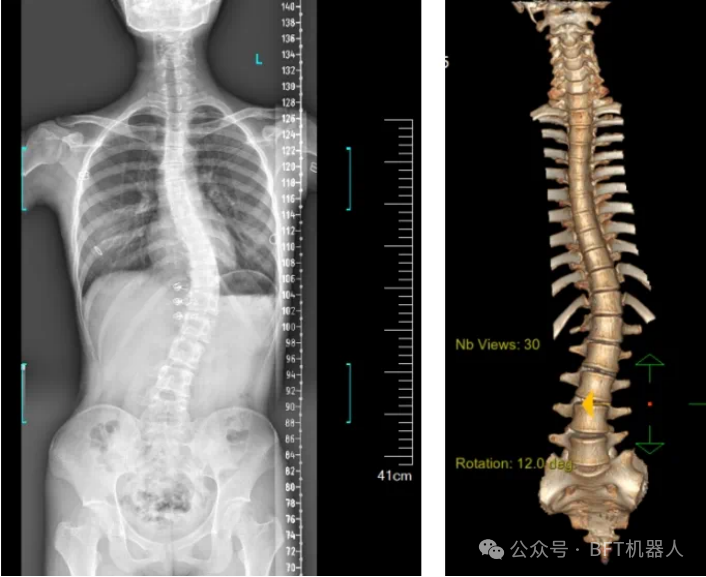

3D机器视觉的脊柱检测图

3D视觉技术可以用于自动化的脊柱侧弯检测。通过使用3D成像设备,如结构光或激光扫描仪,机器人可以快速捕捉老年人的脊柱图像,并利用机器视觉算法分析脊柱的形态和角度,从而判断是否存在侧弯现象。

基于显扬科技HY-HY-X3 3D机器视觉的脊柱侧弯检测系统,能够在无需接触患者的情况下,快速获取患者脊柱的三维图像。该系统使用高精度的3D摄像头,通过结构光或激光扫描技术,捕捉到脊柱的详细形态。系统扫描速度为15Hz,精度达到±0.01mm,结合自研智能算法,能够进行全彩信息学习,还能通过深度摄像头捕捉人体背部的形态变化,转化为对应的脊柱形态,并计算脊柱的弯曲角度,从而了解患者的侧弯程度。这种方法避免了传统X光片检测带来的辐射风险,实现了无辐射、快速、便捷的筛查。还可以根据康疗脊柱侧弯的具体治疗需求制定具体的机器人解决方案,一键解决现今康疗行业脊柱侧弯检测的深耕难点。

针对老年人常见的慢性病和疼痛等问题。BFT平台中的显扬科技开发的3D机器视觉系统,可以对患者的脊柱进行三维空间内的精准定位与测量。通过立体视觉技术,系统能够获取脊柱的精确三维坐标信息,为脊柱侧弯的检测提供数据支持,可以更直观了解脊柱的形态和侧弯程度,从而进行准确的诊断。